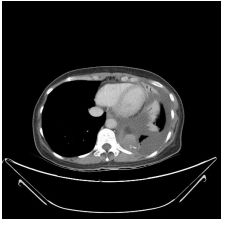

3. This 72-year-old diabetic man was taken to ER for productive cough for 10 days, and rapid progressive dyspnea for 2 days. He also had fever and chill for a week.